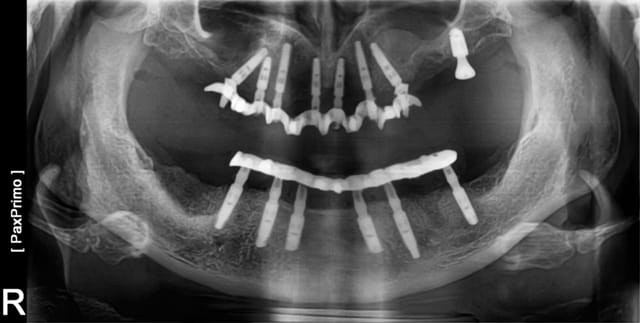

photo 1 lundi

Extractions, pose des implants, pose des multis-units, pose des bridges provisoire en une chirurgie. Cas 1 et 2 implants MIS, 3 BREDENT. Photo du provisoire 1 et 3 prise dans la suite de l'intervention chirurgicale, 2 prise à 48h.

Pano de contrôle à 40 J post op